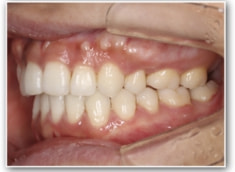

治療前